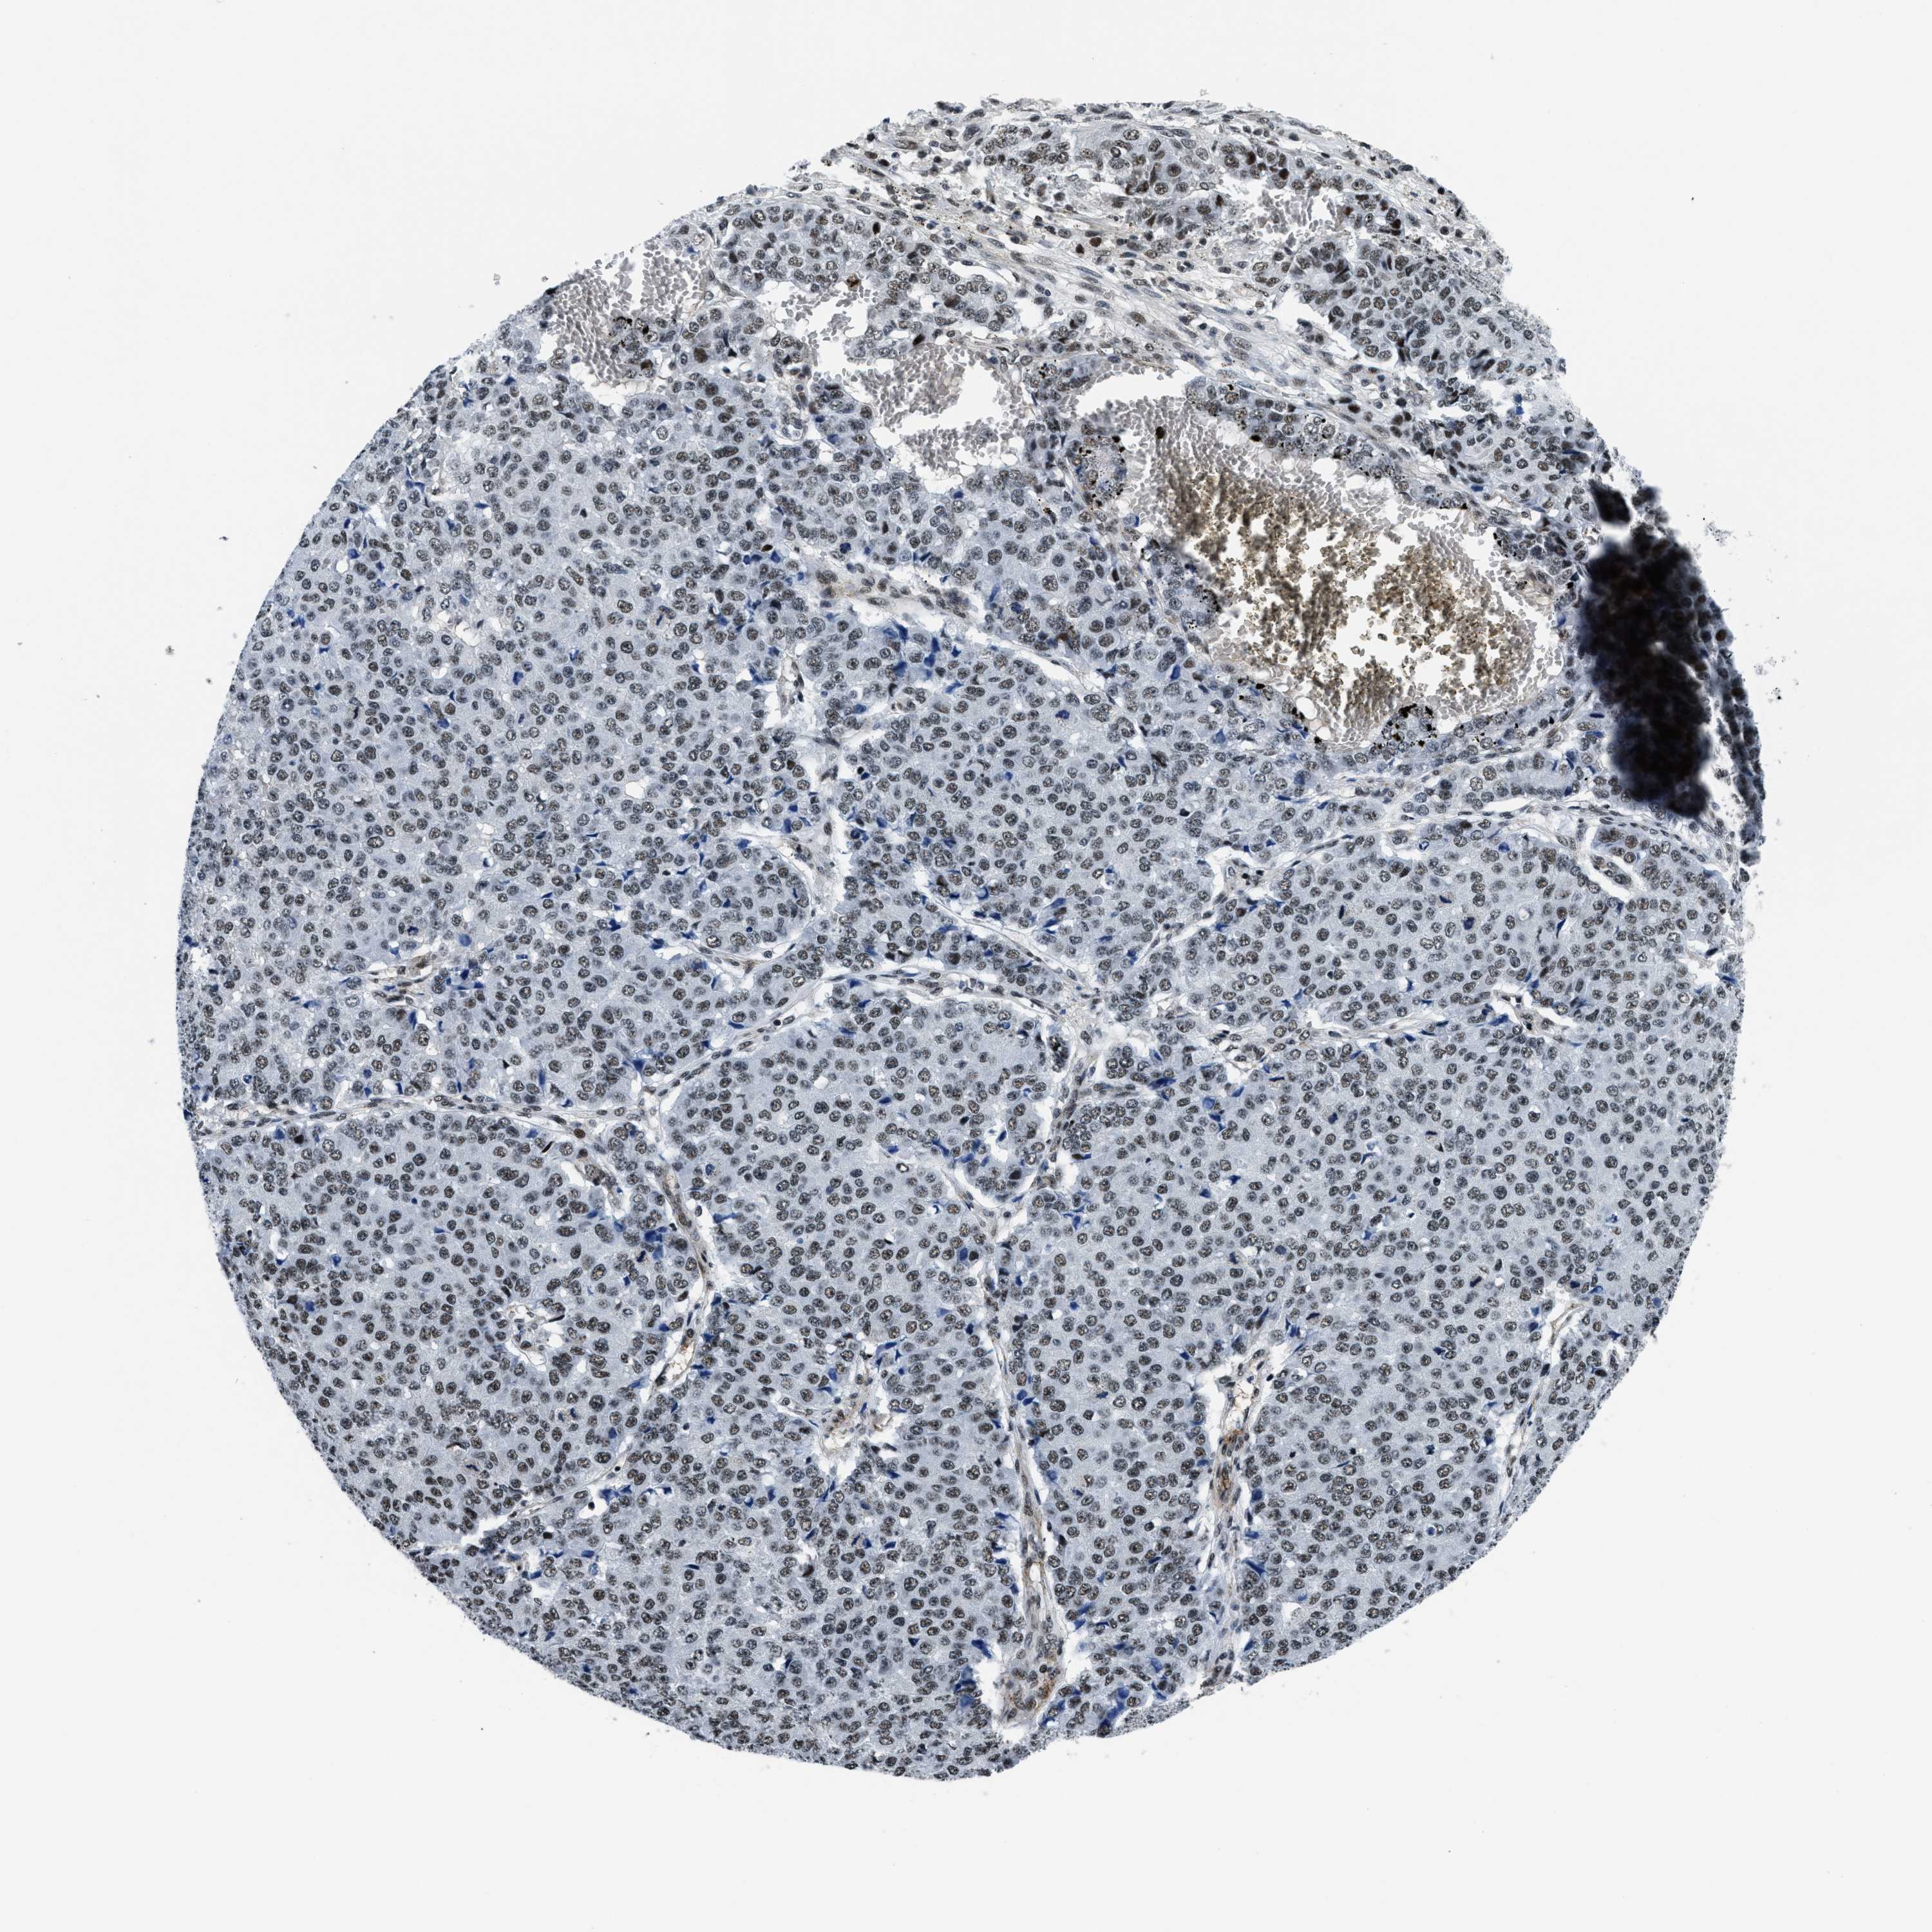

PANCREATIC CANCER - Protein expressioni

A mouse-over function shows sample information and annotation data. Click on an image to view it in a full screen mode. Samples can be filtered based on level of antibody staining by selecting one or several of the following categories: high, medium, low and not detected. The assay and annotation is described here.

Note that samples used for immunohistochemistry by the Human Protein Atlas do not correspond to samples in the TCGA dataset.

Antibody stainingi

Antibody staining in the annotated cell types in the current human tissue is reported as not detected, low, medium, or high, based on conventional immunohistochemistry profiling in selected tissues. This score is based on the combination of the staining intensity and fraction of stained cells.

Each image is clickable and will lead to virtual microscopy that enables deeper exploration of all samples and also displays staining intensity scores, fraction scores and subcellular localization as well as patient and tissue information for each sample.

Antibody HPA018248

Antibody HPA019127

Antibody CAB009196

Staining

High

Medium

Low

Not detected

Intensity

Strong

Moderate

Weak

Negative

Quantity

>75%

75%-25%

<25%

None

Location

Nuclear

Cytoplasmic/membranous

Cytoplasmic/membranous,nuclear

Adenocarcinoma, NOS

Adenocarcinoma, metastatic, NOS